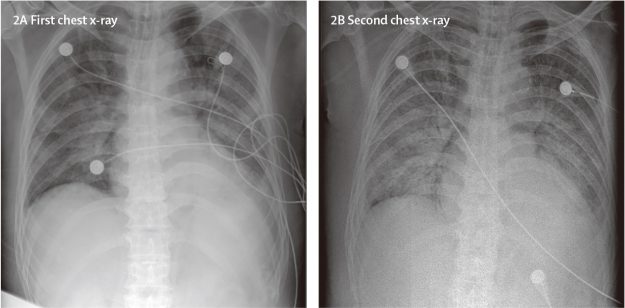

2019-nCoV,一种新的冠状病毒,引起了最近出现在中国武汉的多个肺炎病例。我们报道了这些肺炎病人的流行病学、临床、实验室、影像学等方面的特征以及采取治疗方法和临床结局。2019-ncov感染导致严重呼吸道疾病群集,类似于严重急性呼吸综合征冠状病毒引起的症状,并与ICU入院和高死亡率相关。目前对该疾病的起源、流行病学特征、人类传播持续时间以及临床疾病谱的认识存在不足,需要通过后续研究补充完善。